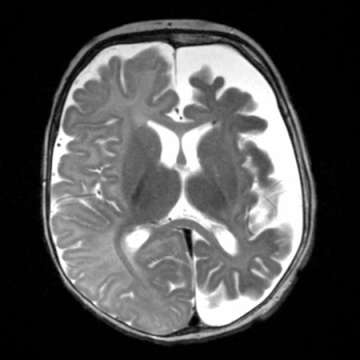

Sturge Weber Syndrome